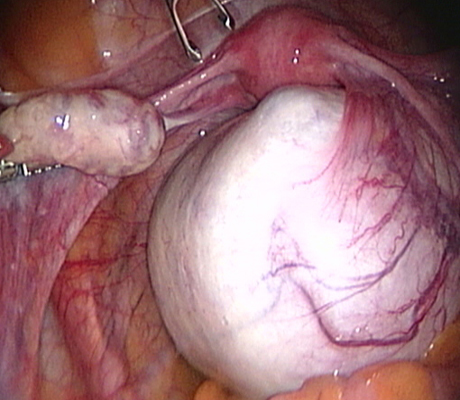

Examples of some pelvic masses dealt with by key-hole surgery.

Pelvic Mass